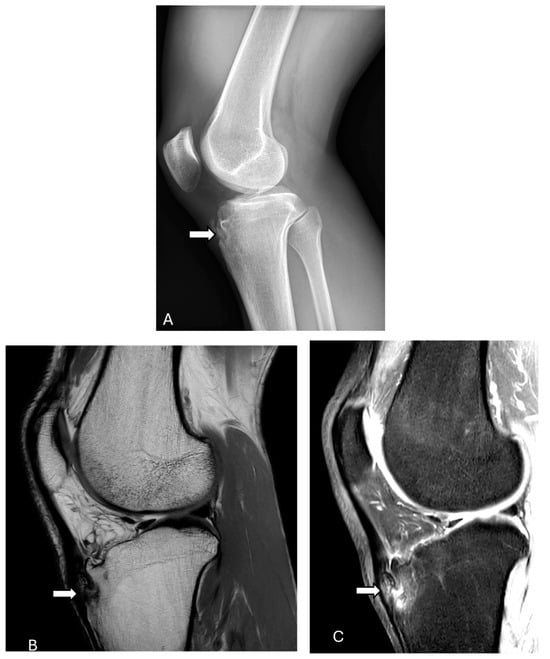

3.6.1. Patellar Tendon Tear